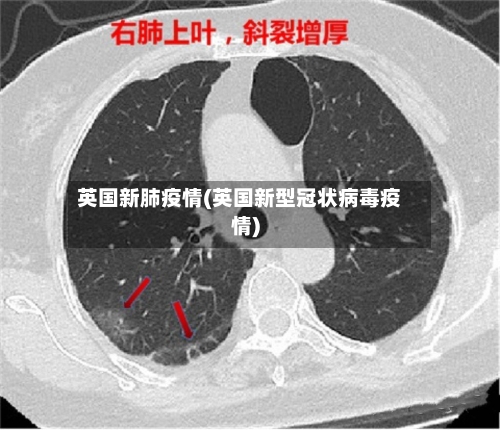

英国新肺疫情(英国新型冠状病毒疫情)

英国国家统计局的数据显示,英国各地感染新冠肺炎病毒的人数创历史新高。其中 ,70岁以上感染者比例达到6%,创下新的历史纪录 。据此前报道,英国国家统计局新冠肺炎疫情调查项目高级统计师卡拉表示 ,奥密克戎亚型突变株BA.2在英国各地的传播导致感染人数迅速增加。

英国:自2月宣布“与新冠共存”计划以来 ,新冠检测阳性者无需自我隔离,政府也不再追踪密切接触者,但疫情数据居高不下 。英国国家统计局(ONS)数据显示 ,英国大约每13人中就有1人确诊。奥密克戎BA.2毒株在英格兰地区快速传播,导致55岁以上群体感染率激增,比此前平均水平高出20倍。

英国。英国国家统计局的最新数据显示,英国大约每13人中就有1人确诊 。4月6日公布的研究结果还显示,奥密克戎BA2毒株正在英格兰地区快速传播 ,导致3月以来55岁以上群体感染率激增 ,比此前平均水平高出20倍。美国。随着奥密克戎BA2毒株的蔓延,全美新冠发病率再次上升 。